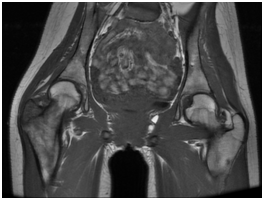

The simple x-ray showed a lytic lesion of the right greater trochanter with well-defined borders and no calcifications within it (Figure 1). The laboratory findings were characteristic of severe protein calorie malnutrition with a normal full blood count and CRP. The magnetic resonance imaging showed signal alteration at the right greater trochanter measuring 3.3 cm in diameter and triangular in morphology, with low signal in T1 and T2. It was well demarcated by a hypointense line and associated with bone marrow oedema of practically the whole of the right neck of femur. We also visualised significant signal changes with acute inflammatory characteristics of the tendons inserting into the right greater trochanter, related to acute tendinopathy in that region (Figure 2).

Figure 1 Initial simple x-ray: lytic lesion of the right greater trochanter.